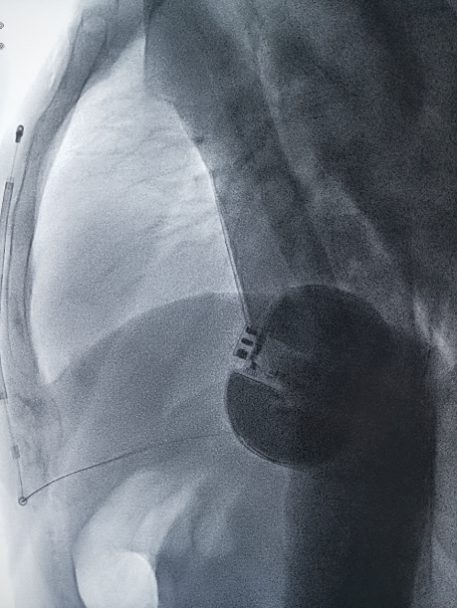

女性患者除颤测试

术中DFT测试

男性患者除颤测试